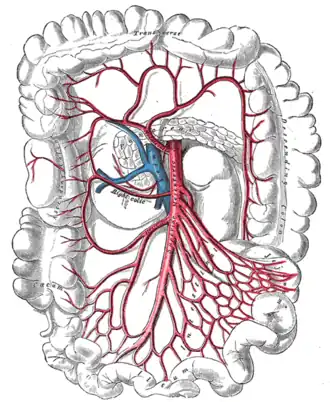

The celiac, superior mesenteric, and inferior mesenteric arteries are the three primary blood vessels that support the digestive tract. Abdominal pain happens because the digestive processes require increased blood flow to the stomach. The stenotic or occluded artery cannot give adequate blood flow. The pain is caused by ischemia of the affected tissues, which do not receive the essential perfusion to perform digestion.[7]

The gastrointestinal system has significant collateral circulation, which may worsen in cases of vascular stenosis. Along with the protection provided by collateral blood flow, the colon possesses various other mechanisms to prevent ischemia, such as opening of all mesenteric capillaries, redistribution of intramural blood supply, and improved oxygen extraction. But if those are exceeded, these defensive mechanisms become overwhelmed and no longer provide protection.[8]